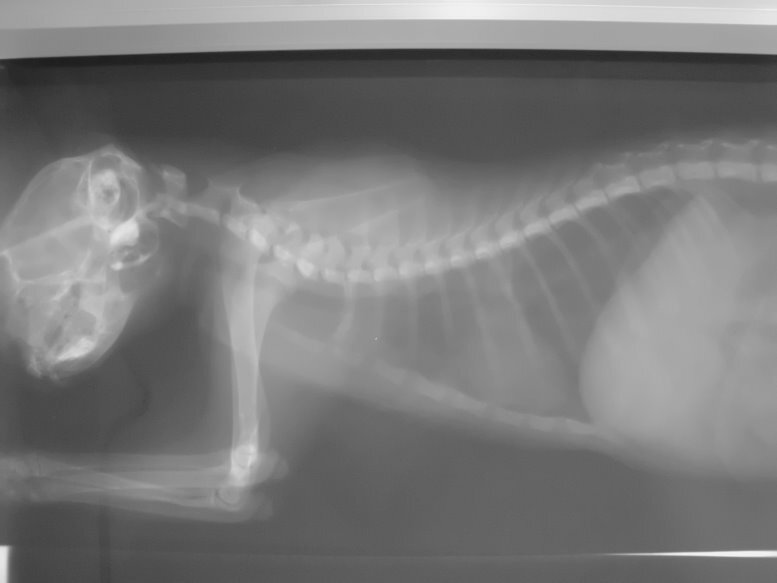

- 編號: 731

主題: 疑似受外力撞擊且有鼻氣管炎的親人小虎斑 申請者姓名: 陳露露 花色: 申請日期: 2012-08-07 03:32:03 申請者部落格: 申請者臉書網址: 所在縣市/合作醫院: 高雄市/樂生動物醫院 治療費用: 4200元 需求人數: 5人 已結案 (2012-12-08 19:10:30) 報名人員: Chinia(已付款)、吳家儀(已付款)、連珮宇(已付款)、龍豪(已付款)、龍豪(已付款)、 候補人員: 小舟、 動物病情說明: 7月23日的深夜,

經過醫生仔細的檢查,

小虎斑有嚴重上呼吸道感染.

流血的部份疑似遭受到外力撞擊造成的!

醫療明細:

1.x ray(兩張) 600

2.驗血 1500

3.住院7 天 2100